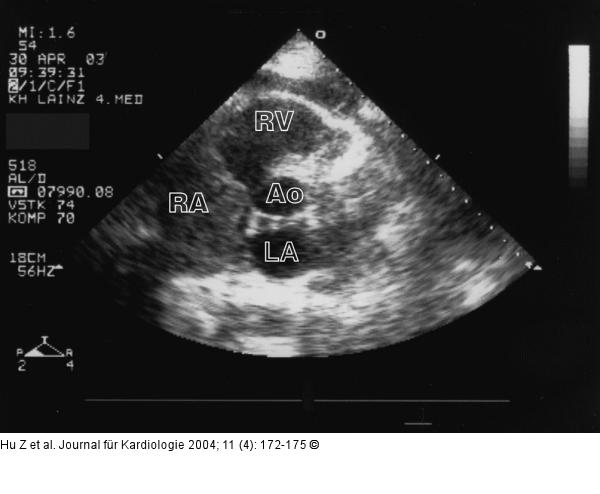

Abbildung 1: Tumorpropagation in den rechten Ventrikel 2-D-Echokardiogramm in der kurzen Achse bei Aufnahme: Ausgedehnter Tumor, der den gesamten rechten Vorhof ausfüllt, bis zur Trikuspidalklappe reicht und den Einstrom in den rechten Ventrikel behindert. |

Abbildung 1: Tumorpropagation in den rechten Ventrikel

2-D-Echokardiogramm in der kurzen Achse bei Aufnahme: Ausgedehnter Tumor, der den gesamten rechten Vorhof ausfüllt, bis zur Trikuspidalklappe reicht und den Einstrom in den rechten Ventrikel behindert. |